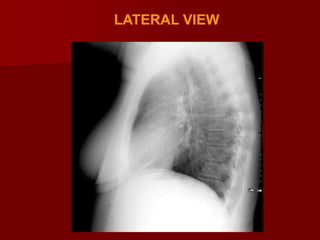

Lateral view

The only view that provides information of

localization of different lobes and segments

 Observation on lateral view include- clear

spaces, vertebral translucency , and outline of

diaphragms.